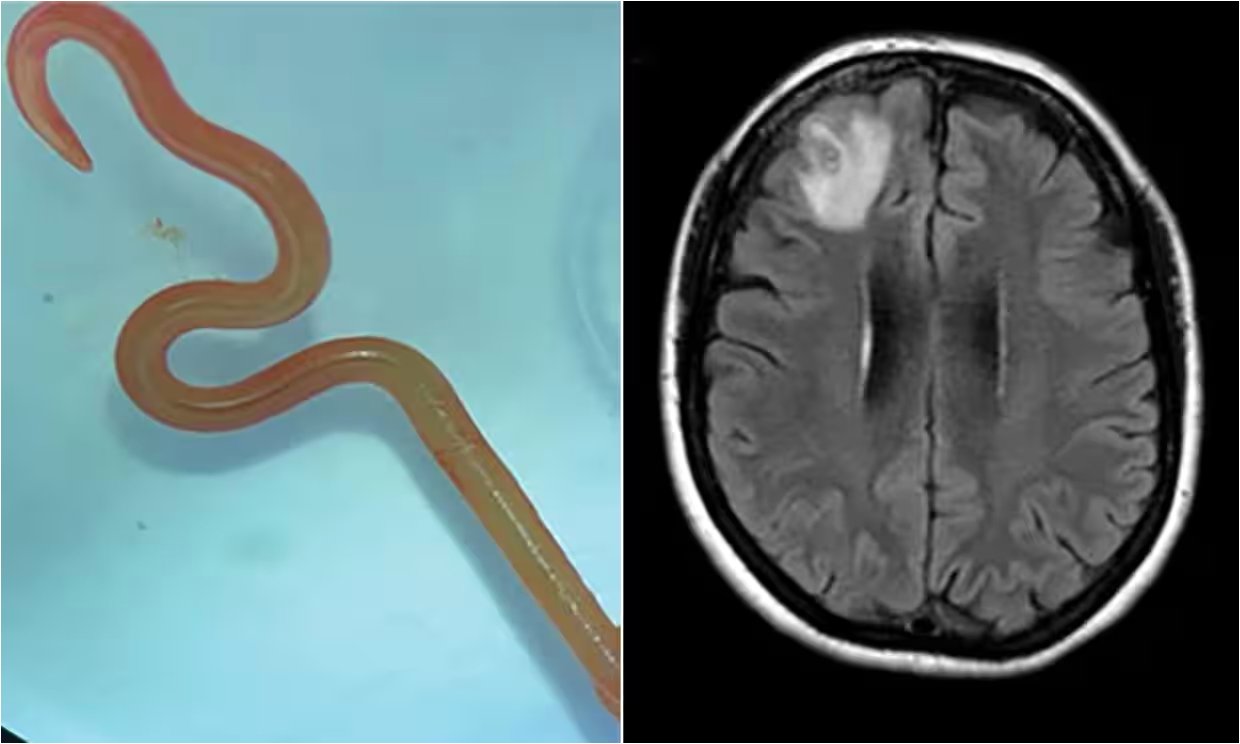

환자는 여러 검사에도 불구하고 기생충 감염의 명확한 흔적을 찾기 어려웠습니다. 세균, 곰팡이, 기생충 항체 검사 등에서 음성 반응이 나왔고, 구충제 처방에도 호흡기 증상이 쉽게 가라앉지 않았습니다. 수개월간 증상이 지속되면서 환자는 우울감과 기억상실까지 겪게 되었습니다. 결국 뇌 MRI 검사를 통해 우측 전두엽에서 병변이 발견되었고, 뇌 조직 검사 결과 살아있는 기생충이 확인되었습니다. 의료진은 뇌 조직에서 약 80mm 길이의 기생충을 제거하는 수술을 시행했습니다.

이 기생충은 원래 호주에 서식하는 카펫비단뱀에 기생하는 선충의 유충 단계로 알려져 있습니다. 환자는 뱀과의 직접적인 접촉은 없었지만, 집 주변에서 야생 채소를 자주 채취해 먹었다고 진술했습니다. 의료진은 환자가 기생충 알에 오염된 식물을 만지거나 섭취함으로써 감염되었을 가능성이 높다고 추정했습니다. 이 기생충 유충은 실험용 쥐에서 4년 이상 생존하는 것으로 알려져 있으나, 인간의 뇌에서 발견된 사례는 이번이 처음입니다.

뇌에서 기생충을 제거하는 수술과 함께 구충제 및 항염증제 치료가 병행되었습니다. 수술 후 6개월이 지나자 환자의 폐와 간 병변은 사라졌고, 백혈구 수치도 정상으로 돌아왔습니다. 또한, 신경정신과적 증상이었던 우울감과 기억상실도 호전되는 경과를 보였습니다. 이 성공적인 치료 사례는 희귀 기생충 감염의 진단과 치료에 대한 중요한 정보를 제공합니다.